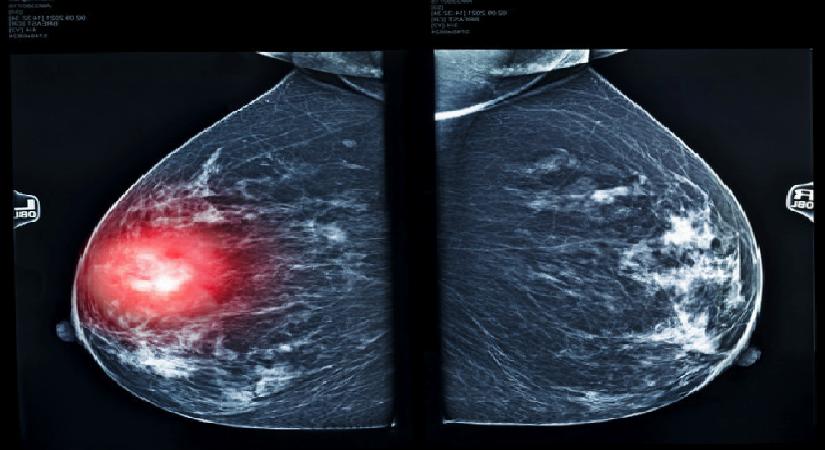

MEME KANSERİ NEDİR?

Meme kanseri, göğüste başlayan bir kanser çeşididir. Hastalığın ciddiyeti kanserin boyutuna, yayılıp yayılmadığına ve genel sıhhat durumunuza bağlıdır.

Meme taraması (mamografi), elle hissedilemeyecek yahut gözle görülemeyecek kadar küçük kanserleri tespit edebilir, bu da tedavinin başarılı olma ihtimalini artırır. Bazen göğüs kanseri bedenin öteki bir bölgesine yayılabilir; buna ikincil (sekonder) göğüs kanseri denir.